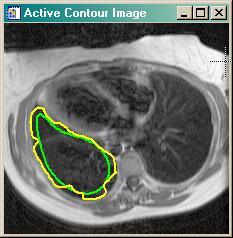

- ACTIVECONTOUR Active contour (or snake) example program. Uses GVF Active Contouring algorithm.